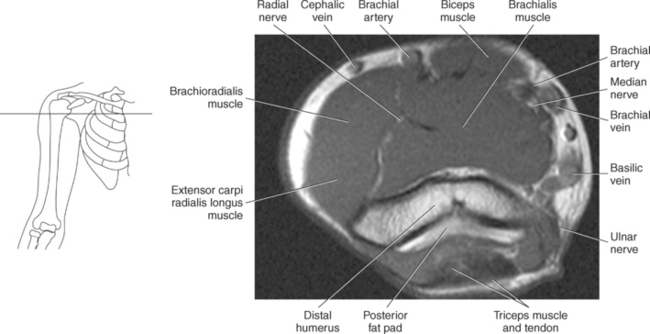

The muscles of the upper arm can be divided into ventral and dorsal groups according to their position. The ventral group contains the biceps brachii, brachialis, and coracobrachialis muscle, and the dorsal group consists of the triceps brachii and anconeus muscles. These muscles are demonstrated in Figures 9.55 through 9.69 and described in Table 9.4.

The biceps brachii muscle is located on the anterior surface of the humerus and acts as a strong flexor of the forearm. The biceps brachii muscle is so named “biceps” because of its two expanded heads of proximal attachment (long and short). The tendon of the long head arises from the supraglenoid tubercle and courses through the intertubercular (bicipital) groove to merge with the tendon from the short head. The short head of the biceps brachii muscle originates from the coracoid process and joins with the long head to create the biceps brachii muscle, which terminates in two tendons. The stronger tendon inserts on the radial tuberosity, and the other tendon creates the bicipital aponeurosis, which radiates into the fascia of the forearm (Figure 9.55).

The brachialis muscle originates from the anterior surface of the distal humerus and covers the anterior surface of the elbow joint before inserting on a roughened area of the proximal and anterior surface of the ulna termed the ulnar tuberosity and the coronoid process. The brachialis muscle is considered to be the most important flexor muscle of the elbow joint (Figure 9.56). The coracobrachialis is a long, narrow muscle located in the superomedial aspect of the arm. It arises from the coracoid process along with the short head of the biceps brachii and extends to insert on the medial surface of the humerus. The primary action of the coracobrachialis muscle is to assist with flexion and adduction of the arm, but it also helps hold the head of the humerus within the joint capsule (Figures 9.56 through 9.67).

The triceps brachii muscle is located on the posterior surface of the humerus and is the main extensor of the forearm. Its name triceps is associated with three heads of proximal attachment (long, lateral, and medial). The long head of the triceps originates from the infraglenoid tubercle of the scapula, the medial head originates from the entire dorsal surface of the humerus distal to the radial groove, and the lateral head arises from the dorsal surface and lateral intermuscular septum of the humerus. All three heads join in a common tendon that inserts on the olecranon process of the ulna and the posterior joint capsule (Figure 9.68). The small, triangular anconeus muscle originates on the lateral epicondyle and crosses obliquely to insert on the dorsal surface of the olecranon process, close to the tendon of the triceps brachii (Figure 9.69). It assists the triceps brachii in extension and also provides dynamic joint stability to the lateral joint capsule. For images of the upper arm, see Figures 9.57 through 9.67.

The primary arteries supplying the shoulder region include the axillary and brachial arteries (Figures 9.34 through 9.45 and 9.144, A). The axillary artery begins at the lateral border of the first rib as a continuation of the subclavian artery. It ends at the inferior border of the teres major muscle, where it passes into the arm and becomes the brachial artery. The axillary artery and its branches supply blood to numerous thoracic and shoulder structures, including the first and second intercostal spaces, axillary lymph nodes, mammary gland in women, and scapular, serratus anterior, pectoral, latissimus dorsi, deltoid, and triceps brachii muscles. The branches of the axillary artery typically include the superior thoracic, thoracoacromial, lateral thoracic, subscapular artery, and anterior and posterior humeral circumflex arteries. The brachial artery is the principal arterial supply to the arm. It courses inferiorly on the medial side of the humerus then continues anterior to the cubital fossa of the elbow. The brachial artery is relatively superficial and palpable throughout its course. It accompanies the median nerve, which crosses anterior to the artery in the middle of the arm. During its course, the brachial artery gives rise to numerous muscular branches, which include the profunda brachii, superior ulnar collateral, and inferior ulnar collateral arteries (Figure 9.144, A).

The veins of the upper arm include the brachial, cephalic, and basilic (Figure 9.146). The two deep brachial veins ascend the arm, one on either side of the brachial artery. The brachial veins begin in the elbow from the union of the ulnar and radial veins and end in the axillary vein near the lower margin of the subscapularis muscle. The two deep brachial veins may join to form one brachial vein during part of their course. The superficial veins of the upper arm include the cephalic and basilic. The cephalic vein courses from the radial side of the dorsal venous arch of the hand and then ascends to the midpoint of the forearm, where it curves around to the ventral surface of the forearm and ascends the lateral aspect of the upper arm, along the anterolateral border of the biceps brachii muscle, to open into the axillary vein, just below the clavicle. It drains the superficial parts of the lateral hand and lateral forearm. The basilic vein originates from the medial end of the dorsal venous arch of the hand. It then ascends the ulnar side of the forearm, along the medial surface of the biceps brachii muscle, in the upper arm, to form the axillary vein. The basilic vein drains the superficial parts of the medial side of the hand and medial side of the forearm. The large axillary vein lies on the medial side of the axillary artery. It extends from the lower border of the teres major muscle to the lateral surface of the first rib to continue as the subclavian vein. The axillary vein receives tributaries that correspond to the branches of the axillary artery (Figures 9.34 through 9.47).

The brachial plexus, also described in Chapter 4, is a large network of nerves that innervate the upper limb (Figures 9.38 and 9.148). It extends from the neck into the axilla. The brachial plexus is formed by the union of the ventral rami of nerves C5-C8 and the greater part of the T1 ventral ramus. The ventral rami from C5 and C6 unite to form a superior trunk, the ventral ramus of C7 continues as the middle trunk, and the ventral rami of C8 and T1 unite to form an inferior trunk. Each of these trunks divides into an anterior and posterior division. The anterior divisions supply the anterior (flexor) parts of the upper limb, and the posterior divisions supply the posterior (extensor) parts of the upper limb. These divisions form three cords (posterior, lateral, and medial) that continue to divide to form the median, ulnar, musculocutaneous, and radial nerves (sequential Figures 9.59 through 9.67 and 9.87 through 9.95). These nerves supply the muscles of the forearm and hand. The median nerve descends the cubital fossa deep to the median cubital vein. It supplies the pronator teres muscle of the arm and all the superficial and deep flexor muscles of the forearm, except the flexor carpi ulnaris muscle. It gives off an anterior interosseous branch that descends within the forearm to supply the flexor digitorum profundus muscle. The median nerve courses through the carpal tunnel of the wrist, typically superficial to the flexor tendons (Figure 9.147). It supplies flexors of the hand, skin of the wrist, thenar eminence, palm of the hand, and sides of the first three digits and lateral half of the fourth. At the elbow, the ulnar nerve passes between the medial epicondyle of the humerus and the olecranon process within the cubital tunnel to enter the medial side of the flexor compartment of the forearm (Figure 9.148). Posterior to the medial epicondyle, the ulnar nerve is superficial and easily palpable. It supplies the flexor carpi ulnaris muscle and the medial side of the flexor digitorum profundus muscle in the forearm before entering the hand. The ulnar nerve passes under the flexor retinaculum, along with the ulnar artery, to enter the palmar compartment of the hand (Figure 9.147). At this point, the ulnar nerve divides into superficial and deep terminal branches that supply the ulnar flexors of the hand as well as the skin on the medial side of the palm, medial half of the dorsum of the hand, fifth digit, and medial half of the fourth digit. The musculocutaneous nerve descends to the lateral side of the arm and elbow to innervate the flexors in the arm and the skin of the forearm, wrist, and thenar region of the hand (Figure 9.146). It emits branches that supply both heads of the biceps brachii muscle, the brachialis muscle, and the elbow joint. It innervates the skin of the dorsal surface of the arm. A continuation of the musculocutaneous nerve is the lateral cutaneous nerve, which terminates into cutaneous branches that supply the skin covering the radial side of the wrist and the thenar eminence. The radial nerve is the largest branch of the brachial plexus. It passes inferolaterally around the body of the humerus in the radial groove (Figure 9.146). It continues inferiorly between the brachialis and brachioradialis muscles to the level of the lateral epicondyle of the humerus, where it divides into deep and superficial branches. The deep branches supply all the extensors in the arm and forearm, and the cutaneous branches innervate the skin on the dorsal side of the arm and hand. The superficial branch, the direct continuation of the radial nerve, is entirely sensory. It supplies skin and fascia over the lateral two thirds of the dorsum of the hand, the dorsum of the thumb, and proximal parts of the lateral three and one half digits on their dorsal surfaces (Figures 9.57 through 9.67, 9.87 through 9.98, and 9.146 and 9.147).